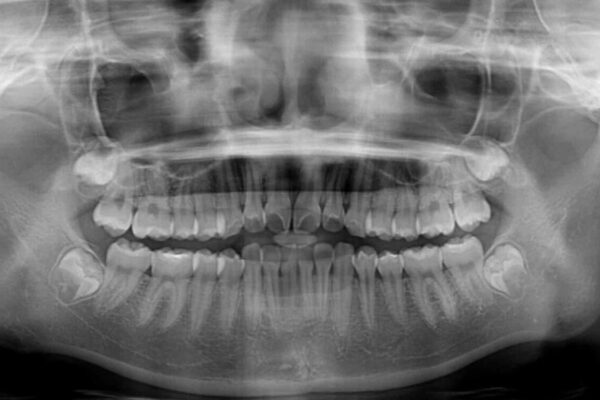

治療前

• インビザラインは使える自信がない ワイヤー装置にて矯正治療 治療前画像